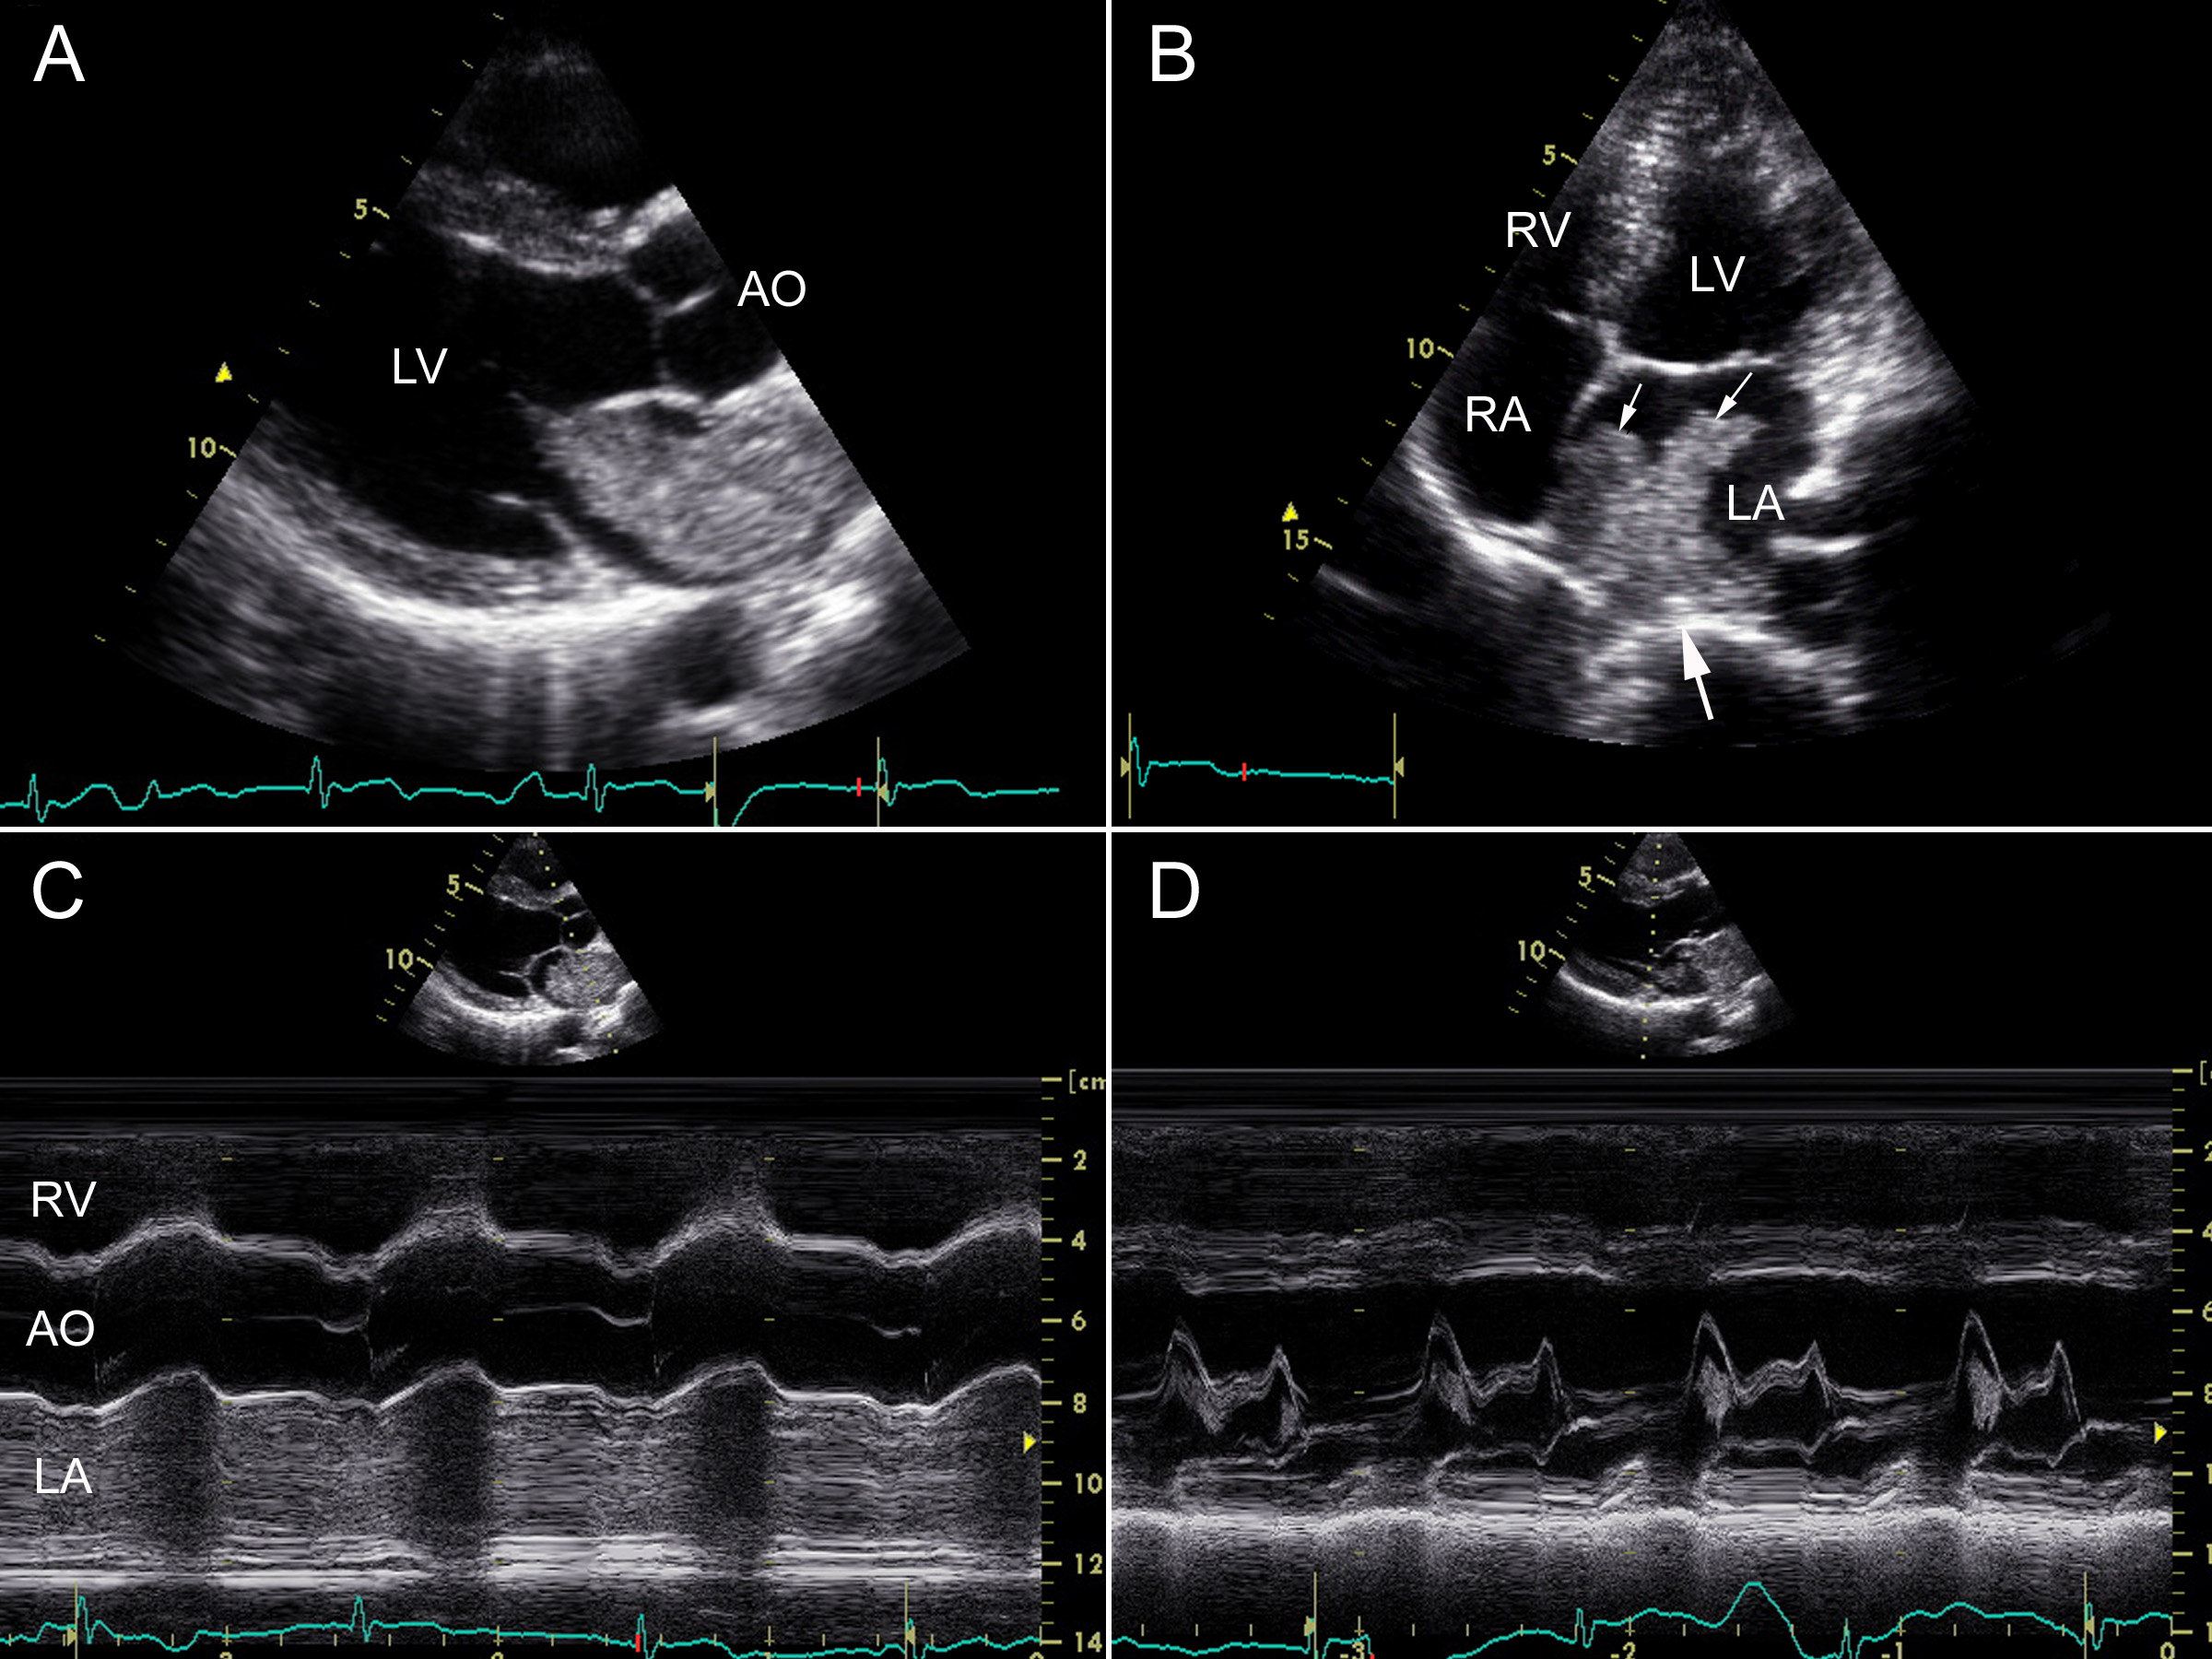

第2节 粘液瘤 | 超声掌中宝

心脏超声诊断的学习分享

sam征阳性M型超声图片

二尖瓣sam征M型示意图

超声心动图